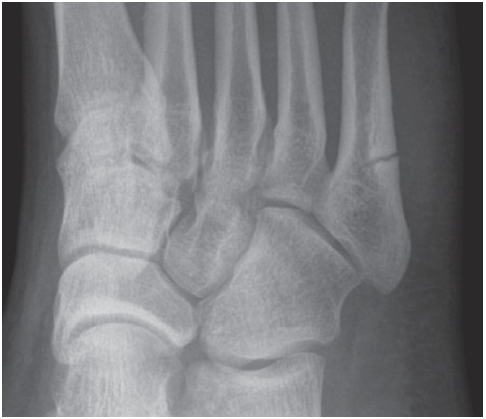

다음은 제5중족골 골절의 네 가지 방사선 영상이다. 손상은 무엇인가?

제5중족골 기저부 골절 (Fractures of the Fifth Metatarsal Base)

① 족저근막의 외측열 부착부의 견열 골절

② 단비골건 부착부의 견열 골절

③ 존스 골절(Jones fracture)

제5중족골 감입 골절(impaction fracture)로, 피로 골절으로 종종 시작된다.

④ 손상 부위 없음

이는 제5중족골 기저부의 정상적인 발달성 골돌기(apophysis)에 해당한다.